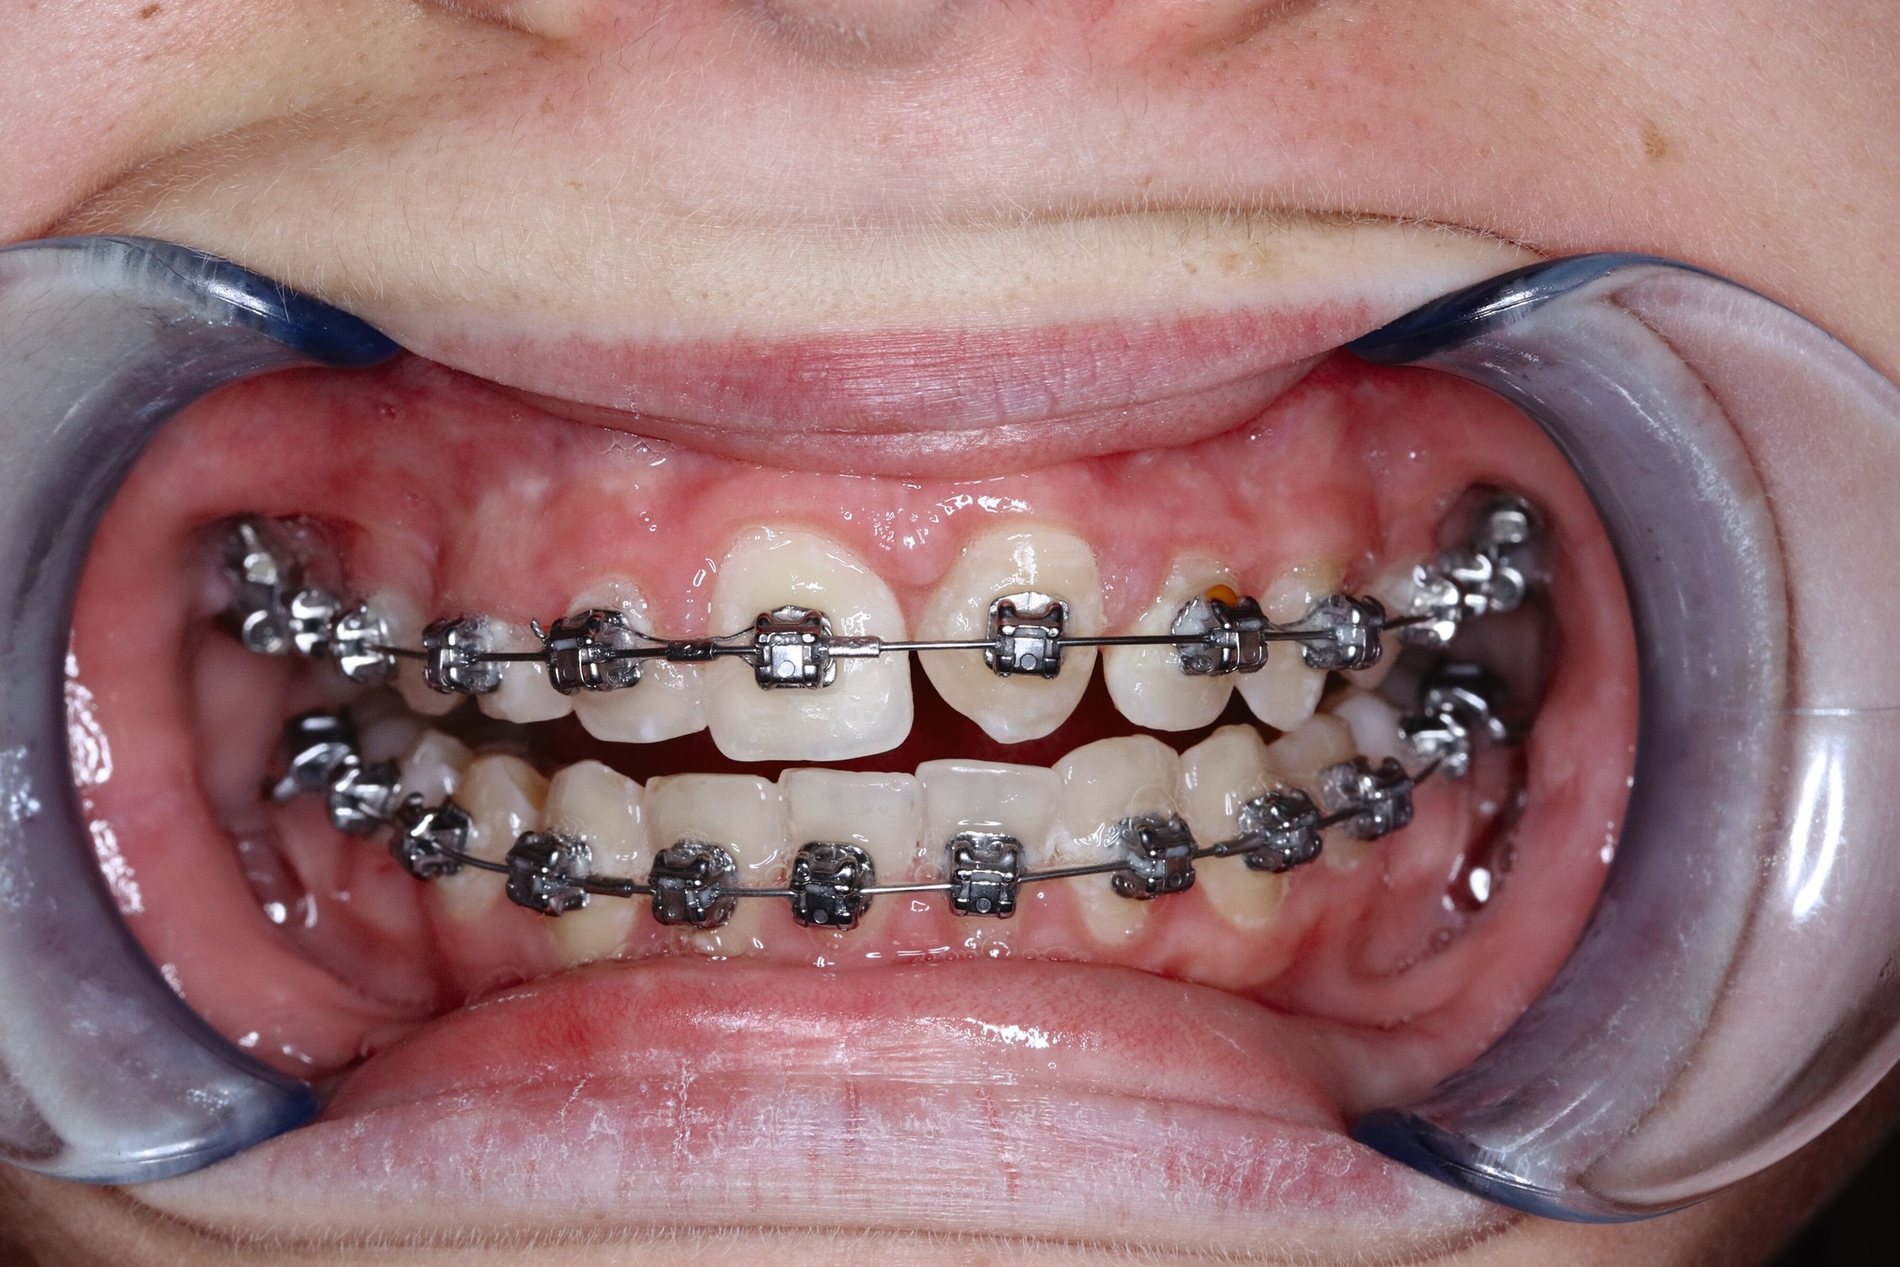

Auf Empfehlung des mitbehandelnden Kieferorthopäden sollte der natürliche Lückenschluss in regio 53 belassen und die autogene Transplantation des verlagerten Eckzahns 13 an die Stelle des verloren gegangenen Zahnes 21 durchgeführt werden. Der Eckzahn 13 wurde etwa einen Monat später in die Region 21 transplantiert und am zuvor eingebrachten kieferorthopädischen Bogen kunststoffadhäsiv fixiert (Abbildung 4).

Der spätere kunststoffadhäsive Aufbau des Zahnes erfolgte nach Erreichen des isogingivalen Niveaus im Vergleich zum Nachbarzahn 11 durch kieferorthopädische Extrusion (Abbildung 5).